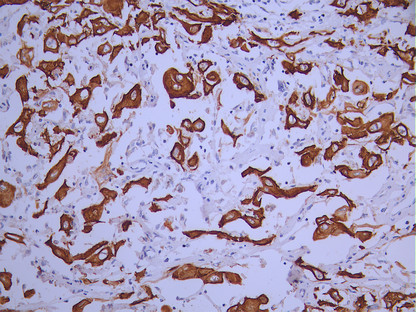

IHC image of CSB-RA954520A0HU diluted at 1:100 and staining in paraffin-embedded human skin tissue performed on a Leica BondTM system. After dewaxing and hydration, antigen retrieval was mediated by high pressure in a citrate buffer (pH 6.0). Section was blocked with 10% normal goat serum 30min at RT. Then primary antibody (1% BSA) was incubated at 4°C overnight. The primary is detected by a Goat anti-rabbit polymer IgG labeled by HRP and visualized using 0.05% DAB.

IHC image of CSB-RA954520A0HU diluted at 1:100 and staining in paraffin-embedded human cervical cancer performed on a Leica BondTM system. After dewaxing and hydration, antigen retrieval was mediated by high pressure in a citrate buffer (pH 6.0). Section was blocked with 10% normal goat serum 30min at RT. Then primary antibody (1% BSA) was incubated at 4°C overnight. The primary is detected by a Goat anti-rabbit polymer IgG labeled by HRP and visualized using 0.05% DAB.